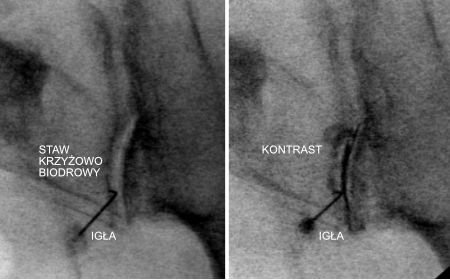

W bólu długotrwałym i uciążliwym najlepszym rozwiązaniem jest precyzyjny zastrzyk przeciwzapalny do stawu krzyżowo biodrowego, czyli tak zwana blokada. Jeżeli jest prawidłowo wykonany, ból znika lub znacznie zmniejsza się około 4. dnia po zabiegu i z reguły więcej się już nie pojawia. Szpara stawu jest wyjątkowo wąska i może być przesłoniona wyroślami kostnymi (zmiany zwyrodnieniowe). Czyni to prawidłowe wprowadzenie igły do stawu bardzo trudne. Badania naukowe dowodzą, że większość zastrzyków wykonanych na ślepo nie trafia do stawu. Dlatego bardzo pomocna w wykonaniu zabiegu jest fluoroskopia (RTG), czyli badanie umożliwiające podgląd i dokładne, celowane wprowadzenie igły do stawu. Podany kontrast potwierdza, że lek dostanie się tam, gdzie powinien. Zabieg taki jest najczęściej krótki i pacjent idzie po nim do domu tego samego dnia. W szczególnych przypadkach, kiedy nie można używać promieniowania,  na przykład w ciąży, taki zabieg można wykonać pod kontrolą rezonansu magnetycznego.

Staw krzyżowo-biodrowy – zastrzyk blokada do stawu krzyżowo biodrowego